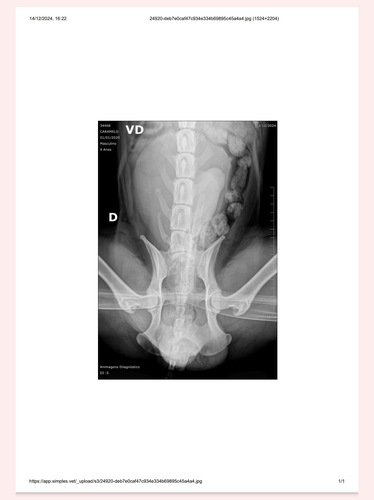

Olá, resgatei esse cachorro no dia 13/12 que foi atropelado próximo a empresa Klabin, recebeu ajuda para que ele fizesse um raio x e que passasse por uma consulta, sendo medicado com a ajuda de duas meninas do grupo da Causa Animal, visto que ele tem fraturas graves ele desapareceu até então.

Hoje 24/12 ele foi encontrado na rede de esgoto da empresa, segue bem machucado e foi trazido para a casa, ele precisa de uma cirurgia urgente se não irá sobreviver, conto com a sua ajuda para salvar a vida dele 🙏🏻